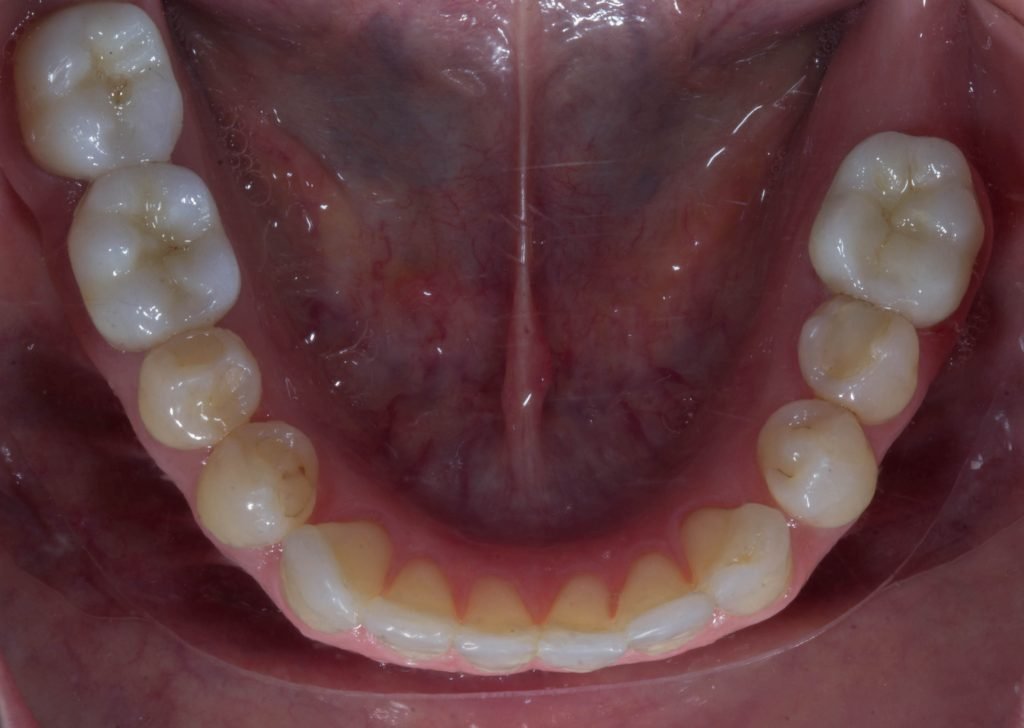

Punto Bajío Casos Clínicos Prótesis Fija sobre Implante unitario Inicio Provisional Final Prótesis Parcial Fija sobre 2 Implantes 2 Implantes Final Prótesis Bucal Removible Inicial Inicial Superior Inicial Inferior Rayos X Inicial Rayos X Inicial Frontal Final Final Superior Final Inferior Prótesis Parcial Fija/ Coronas de Circonio Sonrisa Inicial Foto Inicial Foto Inicial Inferior Foto Final Inferior Foto Final Sonrisa Final Prótesis Total Protesis Inmediatas 1 Protesis Inmediatas 2 Prótesis Removible/ Coronas Metal-Ceramica Carillas Incrustaciones Endodoncia